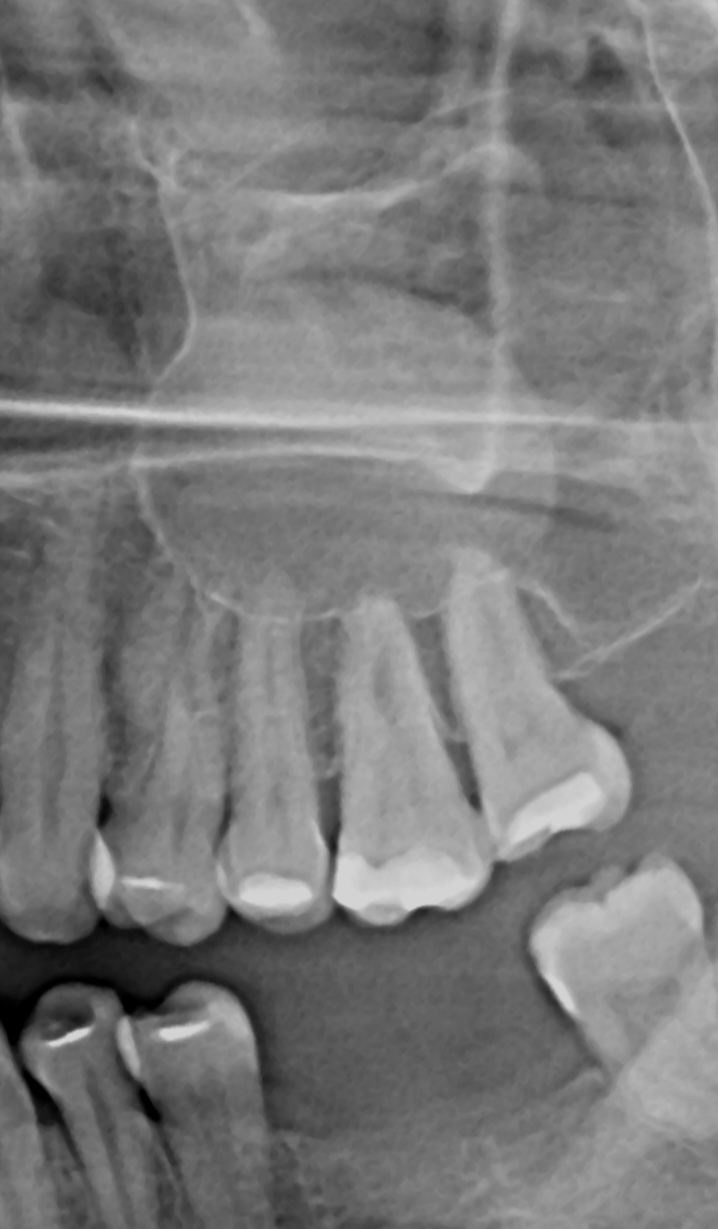

Estrazione preventiva dei denti del giudizio inclusi: è necessaria?

Buonasera Dottore, vorrei un parere chirurgico basato sulla mia ortopanoramica. Mi è stata proposta l'estrazione dei denti del giudizio inferiori (inclusi) a scopo preventivo. Attualmente questi non mi danno alcun problema. Vorrei sapere se, guardando la lastra, ritiene che il rischio di danneggiare i molari vicini o di carie/ infezioni